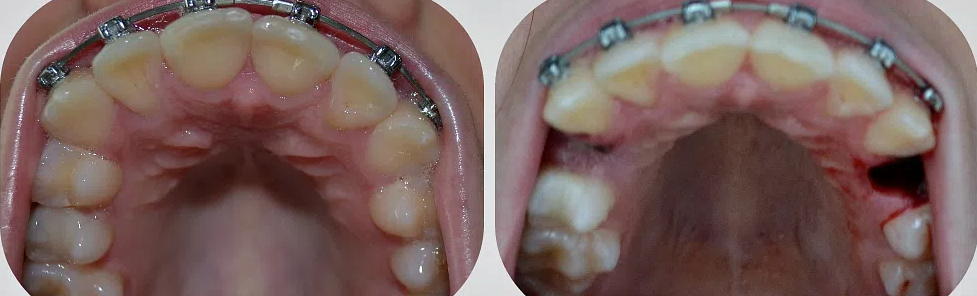

Удаление нижнего зуба мудрости: фото до и после